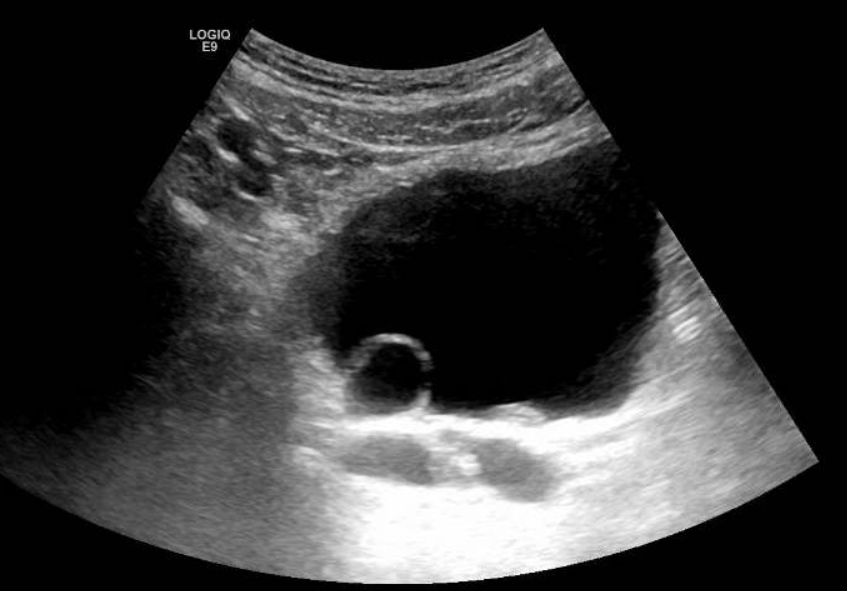

Se solicita ecografía abdominal donde se observa el riñón derecho de tamaño normal, con adelgazamiento parenquimatoso difuso secundario a ureterohidronefrosis severa que se extiende hasta la unión vesicoureteral, donde se visualiza una lesión anecoica intravesical, en relación con el ureterocele ya conocido, que condiciona el cuadro obstructivo.